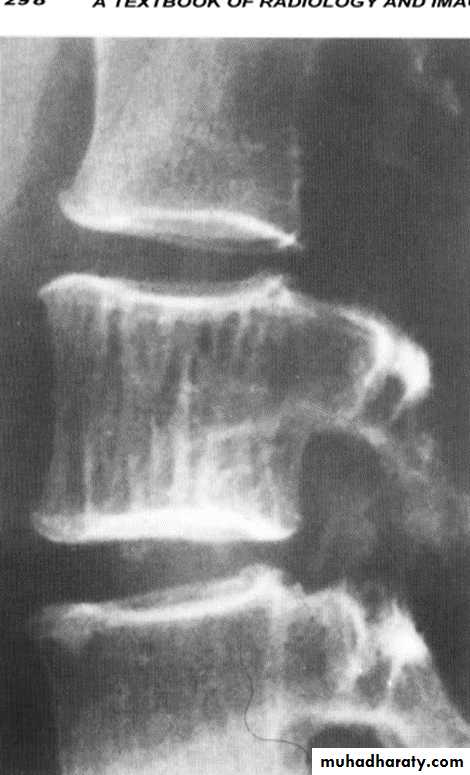

Gibbous deformity wedging of the vertebra (anterior loss of vertebral height)

Seen in TB infection of vertebra

Potts disease also known as tuberculous spondylitis, refers to vertebral body and intervertebral disc involvement with tuberculosis (TB)

Gibbus deformity is a short-segment thoracolumbar kyphosis causing sharp angulation.

Spondylolysis and spondylolisthesis

Spondylolisthesis: is a term denoting fore ward or backward movement of a vertebra relative to the vertebral segment below, typically due to spondylolysis (pars interarticularis defects) .Spondylolysis: Spondylolysis is a defect in the pars interarticularis of the neural arch, the portion of the neural arch that connects the superior and inferior articular facet in which cause defect in the neck of scotty dog .

scotty dog sign refers to the normal appearance of the lumbar spine when seen on oblique radiographic projection. On oblique views, the posterior elements of vertebra form the figure of a Scotty dog with:

the transverse process being the nose

the pedicle forming the eye

the inferior articular facet being the front leg

the superior articular facet representing the ear

the pars interarticularis (the portion of the lamina that lies between the facets) equivalent to the neck of the dog.